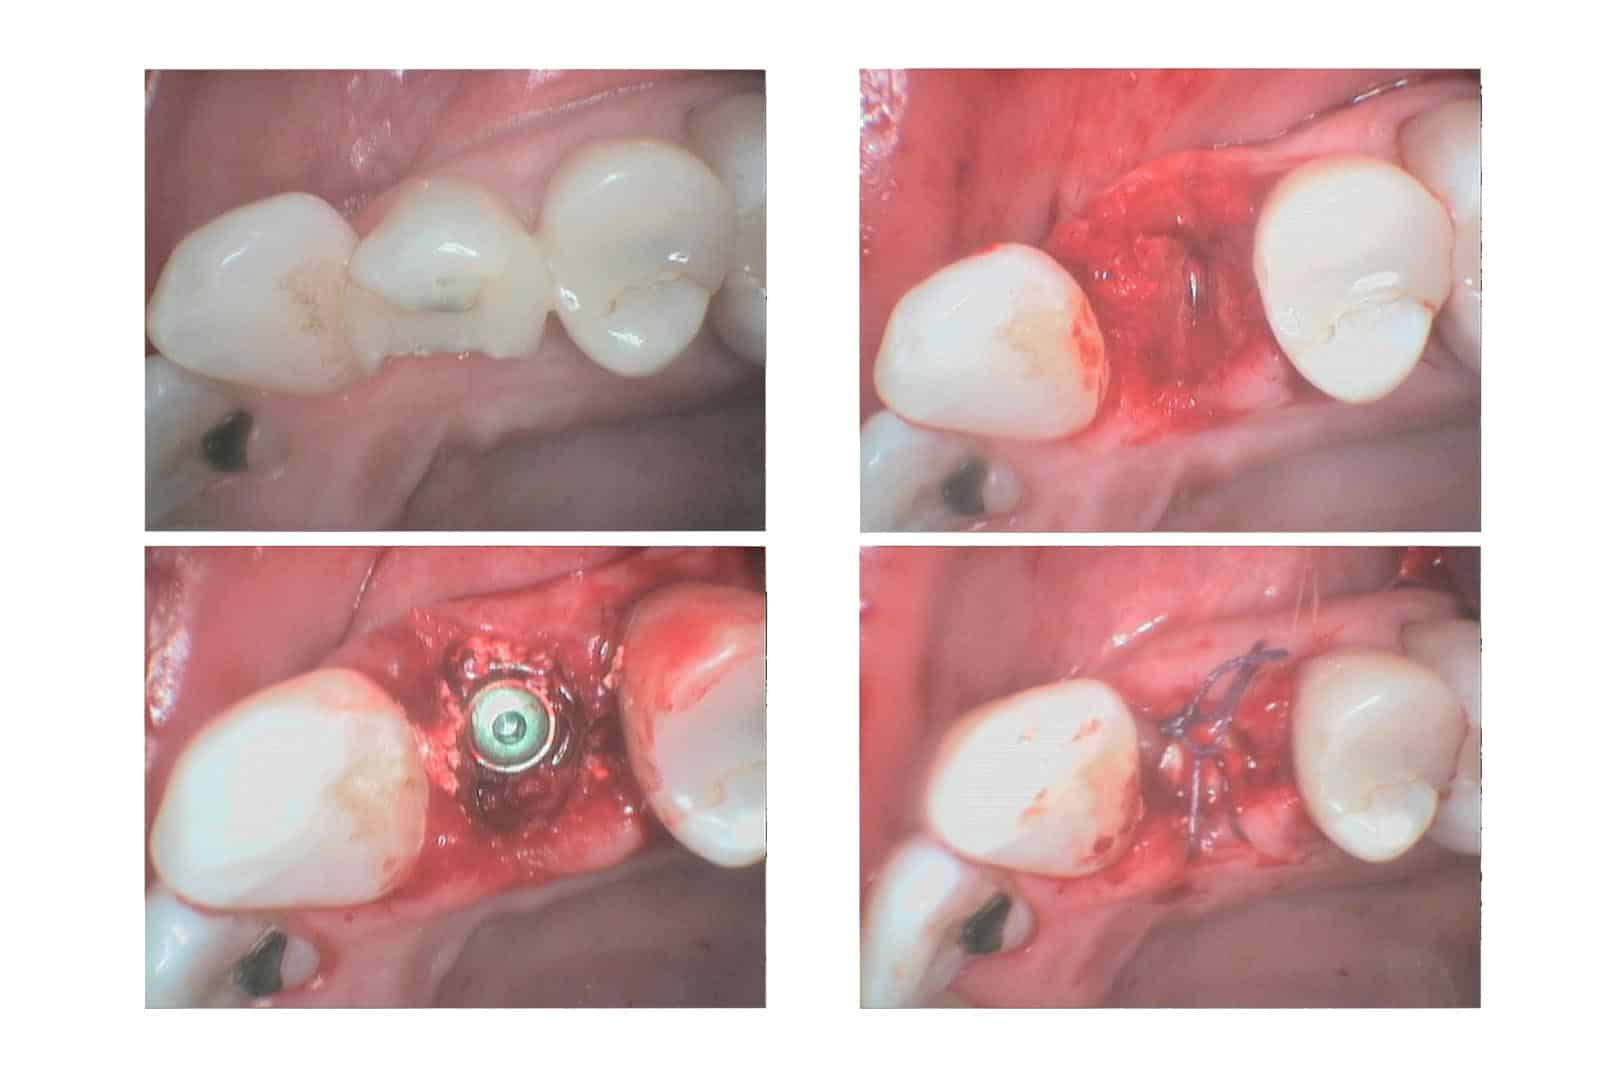

Som ved alle andre behandlinger, vil problemer med tannimplantat også måtte kartlegges for å få et overblikk over situasjonen og avdekke årsak, symptomer og omfang av skaden som har oppstått. Undersøkelsen vil avklare hva slags behandling som må iverksettes. Årskaer for problemer med implantat kan både omfatte kjevedel og tyggedel. Typiske komplikasjoner for kjevedel kan være tannkjøttsykdom, frakturer eller infeksjon. Ved tyggedel kan det ofte dreie seg om løsnet tyggedel, frakturer eller bruksvansker med ny tyggeløsning.

Ved problemstillinger knyttet til implantatbehandling kan det være flere behandlinger som vil være aktuelle. Vi deler gjerne behandlingen inn basert på om det er tyggedel eller kjevedel som er påvirket.

Problemer tilknyttet kjevdel

Ved problemer tilknyttet kjevedel kan det være visse begrensninger for behandling. Er det snakk om tannsykdom, kan dette medføre at tannimplantatet nå er løst og må fjernes.

Skyldes skaden fraktur ved kjevedelen må dette fjernes. Fra der må det vurderes om det kan bli satt inn nytt implantat og hvorvidt prognosen er god for tyggedelen.

Skader som dreier seg om redusert fest rundt implantatet vil som oftest gå ut på å igangsette tannkjøttbehandling slik at spredning av sykdommen ikke fortsetter.

I noen tilfeller kan området der implantatet ble operert inn bli infisert. Dessverre innebærer dette i de fleste tilfeller at implantatet må fjernes. Deretter må det bli gjort en ny vurdering på om det kan settes inn nytt implantat eller ikke.